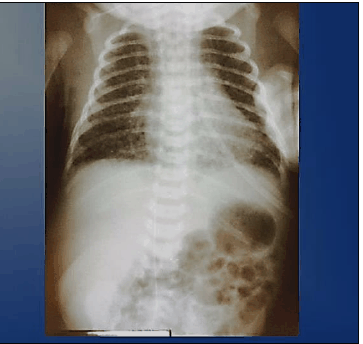

Recém-nascido prematuro, 28 semanas, dá entrada na Unidade de Terapia Intensiva (UTI) Neonatal em CPAP com FiO2 de 30%, hemodinamicamente estável, com peso 1.000 g, nascido de parto cesáreo, indicado por eclâmpsia, Apgar 6/8. A gasometria arterial inicial evidencia os seguintes resultados: pH 7,36; pCO2 33; pO2 84; HCO3 19,8; BE –5,6; e, satO2 94%. De acordo com as informações anteriores, bem como a radiografia de tórax apresentada, qual a conduta indicada em relação ao quadro respiratório da admissão?